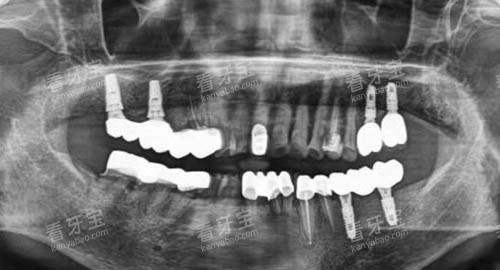

?智能化种植牙:这是其重点宣传的特色项目。利用CBCT更准一些获取颌骨数据,结合口扫和智能化导板技术,实现小创口、更准一些的种植手术。适合多颗牙缺失、半口/全口无牙的患者。患者反馈:“手术比想象中快,肿得不强”、“用了导板,心里踏实点”。

?种植牙: 单颗种植总费用(含种植体、基台、牙冠)通常在 8000元 - 18000元 或更高。价格受种植体品牌(如韩国奥齿泰、登腾,美国皓圣,瑞士ITI,瑞典诺贝尔等)、牙冠材料、是否需植骨等因素综合影响。洁恩口腔常推出“种植牙套餐”,需仔细了解套餐包含的具体项目。